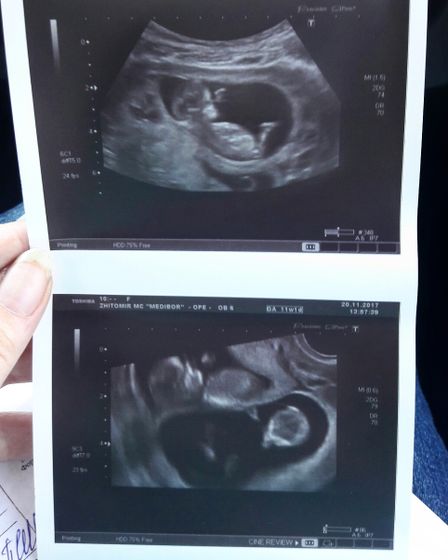

ну вот и прошли мы первое плановое узи. все хорошо, все в пределах нормы. у одного сердцебиение 161 удар в минуту, у второго 147. мои крошки уже 4,75 и 5,1 см. муж от узи в восторге(был со мной). давно не видела его таким счастливым, пол дня целует мне пузик? завтра осталось сдать кровь, еще раз убедиться, что все хорошо и все… можно дальше спокойно носить своих бусинок❤

Скажите, а это платное УЗИ или вы отдельно проходили где то?. Чтобы с мужем пустили и хорошего качества, как у вас )

это обычное плановое узи. сама удивилась, когда и мужа пустили и фотографии сделали?